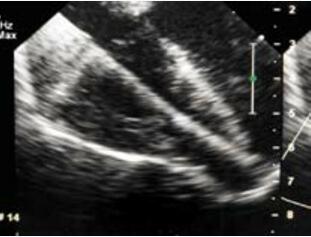

改进也针对复杂解剖的心尖部缺损,笔者称之为“逆向封堵”。虽然病例罕见但是有时会有伴有巨大心尖部壶腹需要较大封堵器方能完成的病例。有时候很值得怀疑这种病人是否能够局部封闭。存在一个缺损隧道,右室肌小梁部存在射流束。隧道方向与右房-右室轴线平行,垂直于右室前壁到缺损之间的轴线,因此根据笔者们的经验穿刺右室前壁通过经典方法穿过缺损极难(图10-48)。如果不改变导丝方向或者在心脏扭曲角度下穿刺前壁将无法通过此类缺损,而且该部位的肌小梁结构可能会不断缠绕导丝,此时由于输送系统是有弹性的,封堵也会受阻。如果遇到此类患者可以通过右房途径进行,切口可在右侧肋间进行。笔者利用一个更简单有效的方式进行。心脏上部拖出切口而不破坏TEE图像暴露室间沟(缺损壶腹部所在),延右室轴线直接穿刺进入通过缺损(图10-49)。而且隧道封堵的完成按照标准方式进行(图10-50)。在提供的病例中笔者选用了一个SQFDQ-Ⅰ14mm的封堵器,封闭了一个2岁患儿 的缺损。值得一提的是,笔者的病人没有任何并发症,没有左室出血危险。在笔者印象中患儿年龄也不比其他方法完成的患者年龄大。

在超声透声图像欠佳或者发生与心尖部缺损封闭相关的其他并发症时,特别是成人患者、数个肌部缺损情况下,可以考虑“杂交”方法和介入方法结合进行(图10-51,图10-52)。笔者遇到一例成人肌部室间隔缺损患者,利用杂交手术的方法由于超声图像不清晰导丝无法通过缺损(胸骨正中小切口,心脏上部难以拖出、操作过程中TEE图像无法显示缺损)。